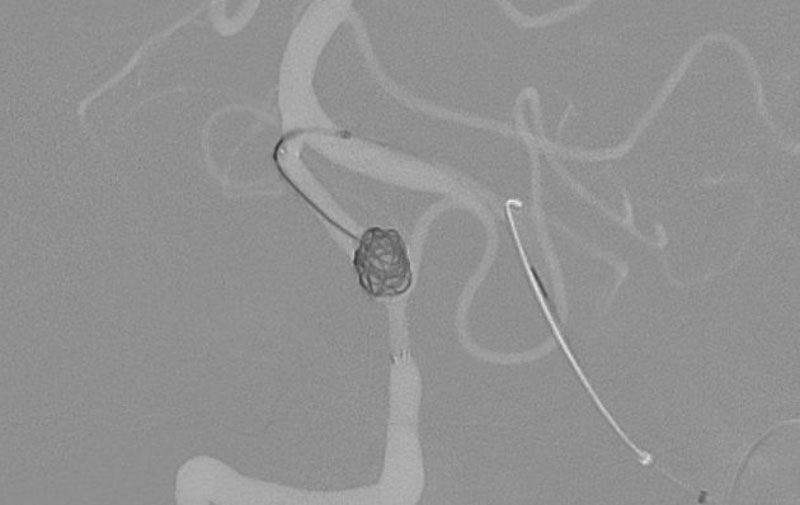

'25年11月

くも膜下出血

左中大脳動脈瘤破裂

40代

救急外来

No.1596 手術前

No.1596 手術中

No.1596 手術後